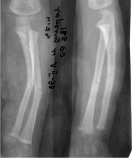

*!Ұсынылған

балтыр сүйектерінің рентгенограммасында

сынық асық жіліктің қай бөлімінде

орналасқан?

*проксималды диафиз

*проксималды метафиз

*дисталды диафиз

*дисталды метафиз

*дисталды эпифиз